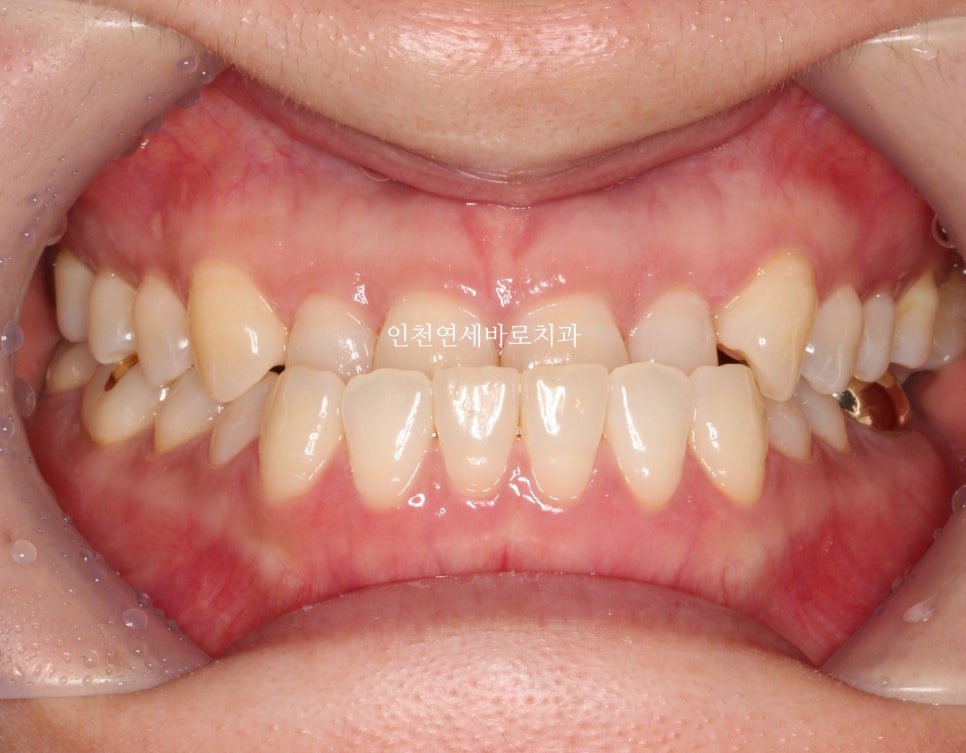

치료기간은 조금 길게 걸렸지만 앞니 관계는 예쁘게 마무리

교합도 잘 마무리 되었고, 현재는 화살표 부분의 임플란트를 완성하기 위해 기다리는 중입니다.

양악수술은 아니기에 큰 변화는 아니지만 안모의 개선을 확인 가능할겁니다.